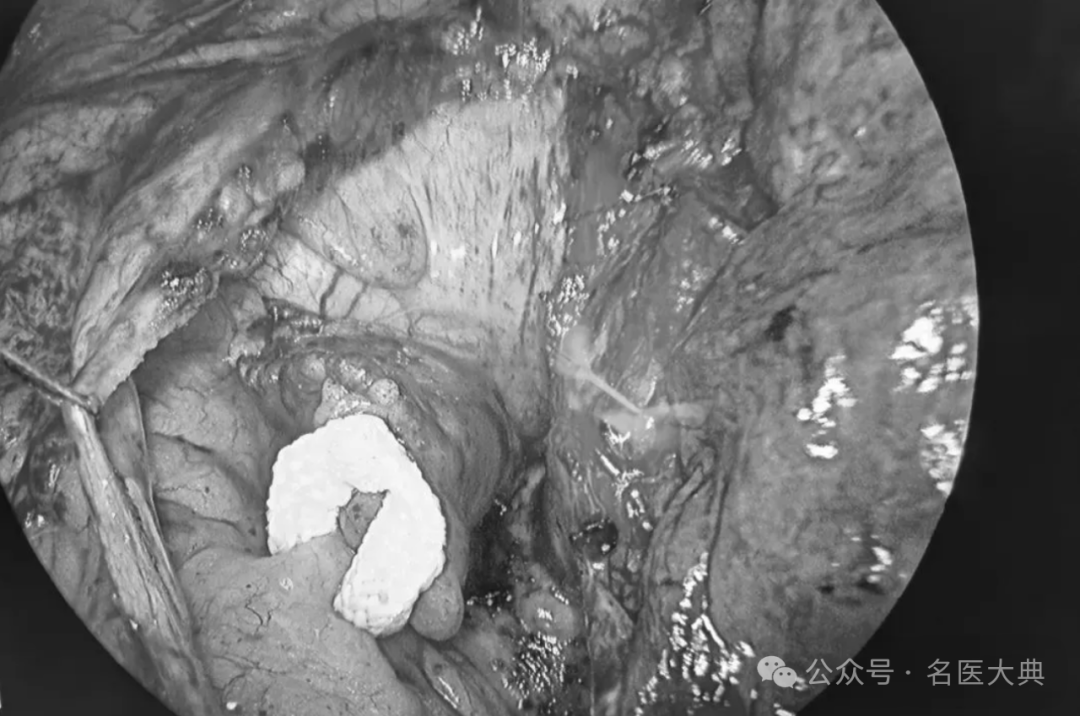

患者为51岁男性,因间断心悸10年、近期频发晕厥就诊。心脏超声显示左心房直径达48mm,CHA2DS2-VASc评分4分,提示其卒中风险是非房颤人群的5-17倍。在规律药物治疗效果有限的情况下,贾一新团队采用 “一站式” 手术策略:经胸腔镜完成双极射频消融恢复窦性心律,同时应用C-Clip®pro精准闭合左心耳根部,从源头消除血栓隐患。术后患者恢复良好,已顺利出院。

本次手术的核心创新在于国产第二代左心耳闭合系统C-Clip®pro的应用。与前代相比,其三大设计优化显著提升了手术安全性和效率:

术中实时角度调节:通过手柄旋钮可动态调整输送器头端角度,适应复杂左心耳解剖结构,避免反复进出创口带来的风险。

体外安全释放机制:采用 “抽线栓” 设计,无需胸腔内剪线即可完成释放,降低操作复杂度和出血风险。

微创化输送系统:头端设计更紧凑,手术切口直径进一步缩小,契合现代微创理念。

贾一新教授评价称:“C-Clip®pro的可调角度设计和体外释放机制,显著提升了复杂病例的处理能力,尤其在左心耳形态不规则时优势明显。”